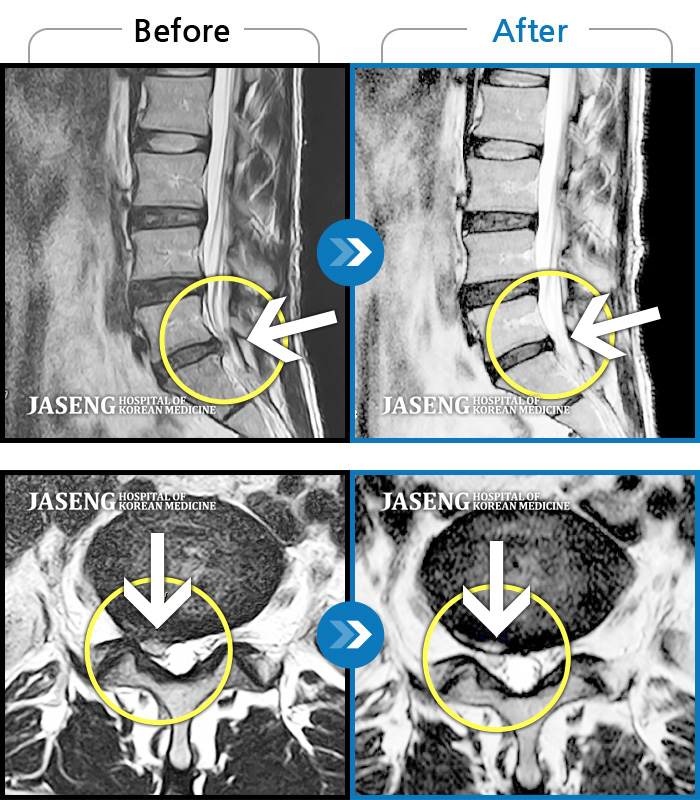

허리디스크

강남 · 이남우 원장

수년간 지속되어온 만성적인 허리통증이 최근 들이 치료에도 반응하지 않고 더욱 심해졌다.

촬영시기

2022.06.21 ~ 2024.08.19